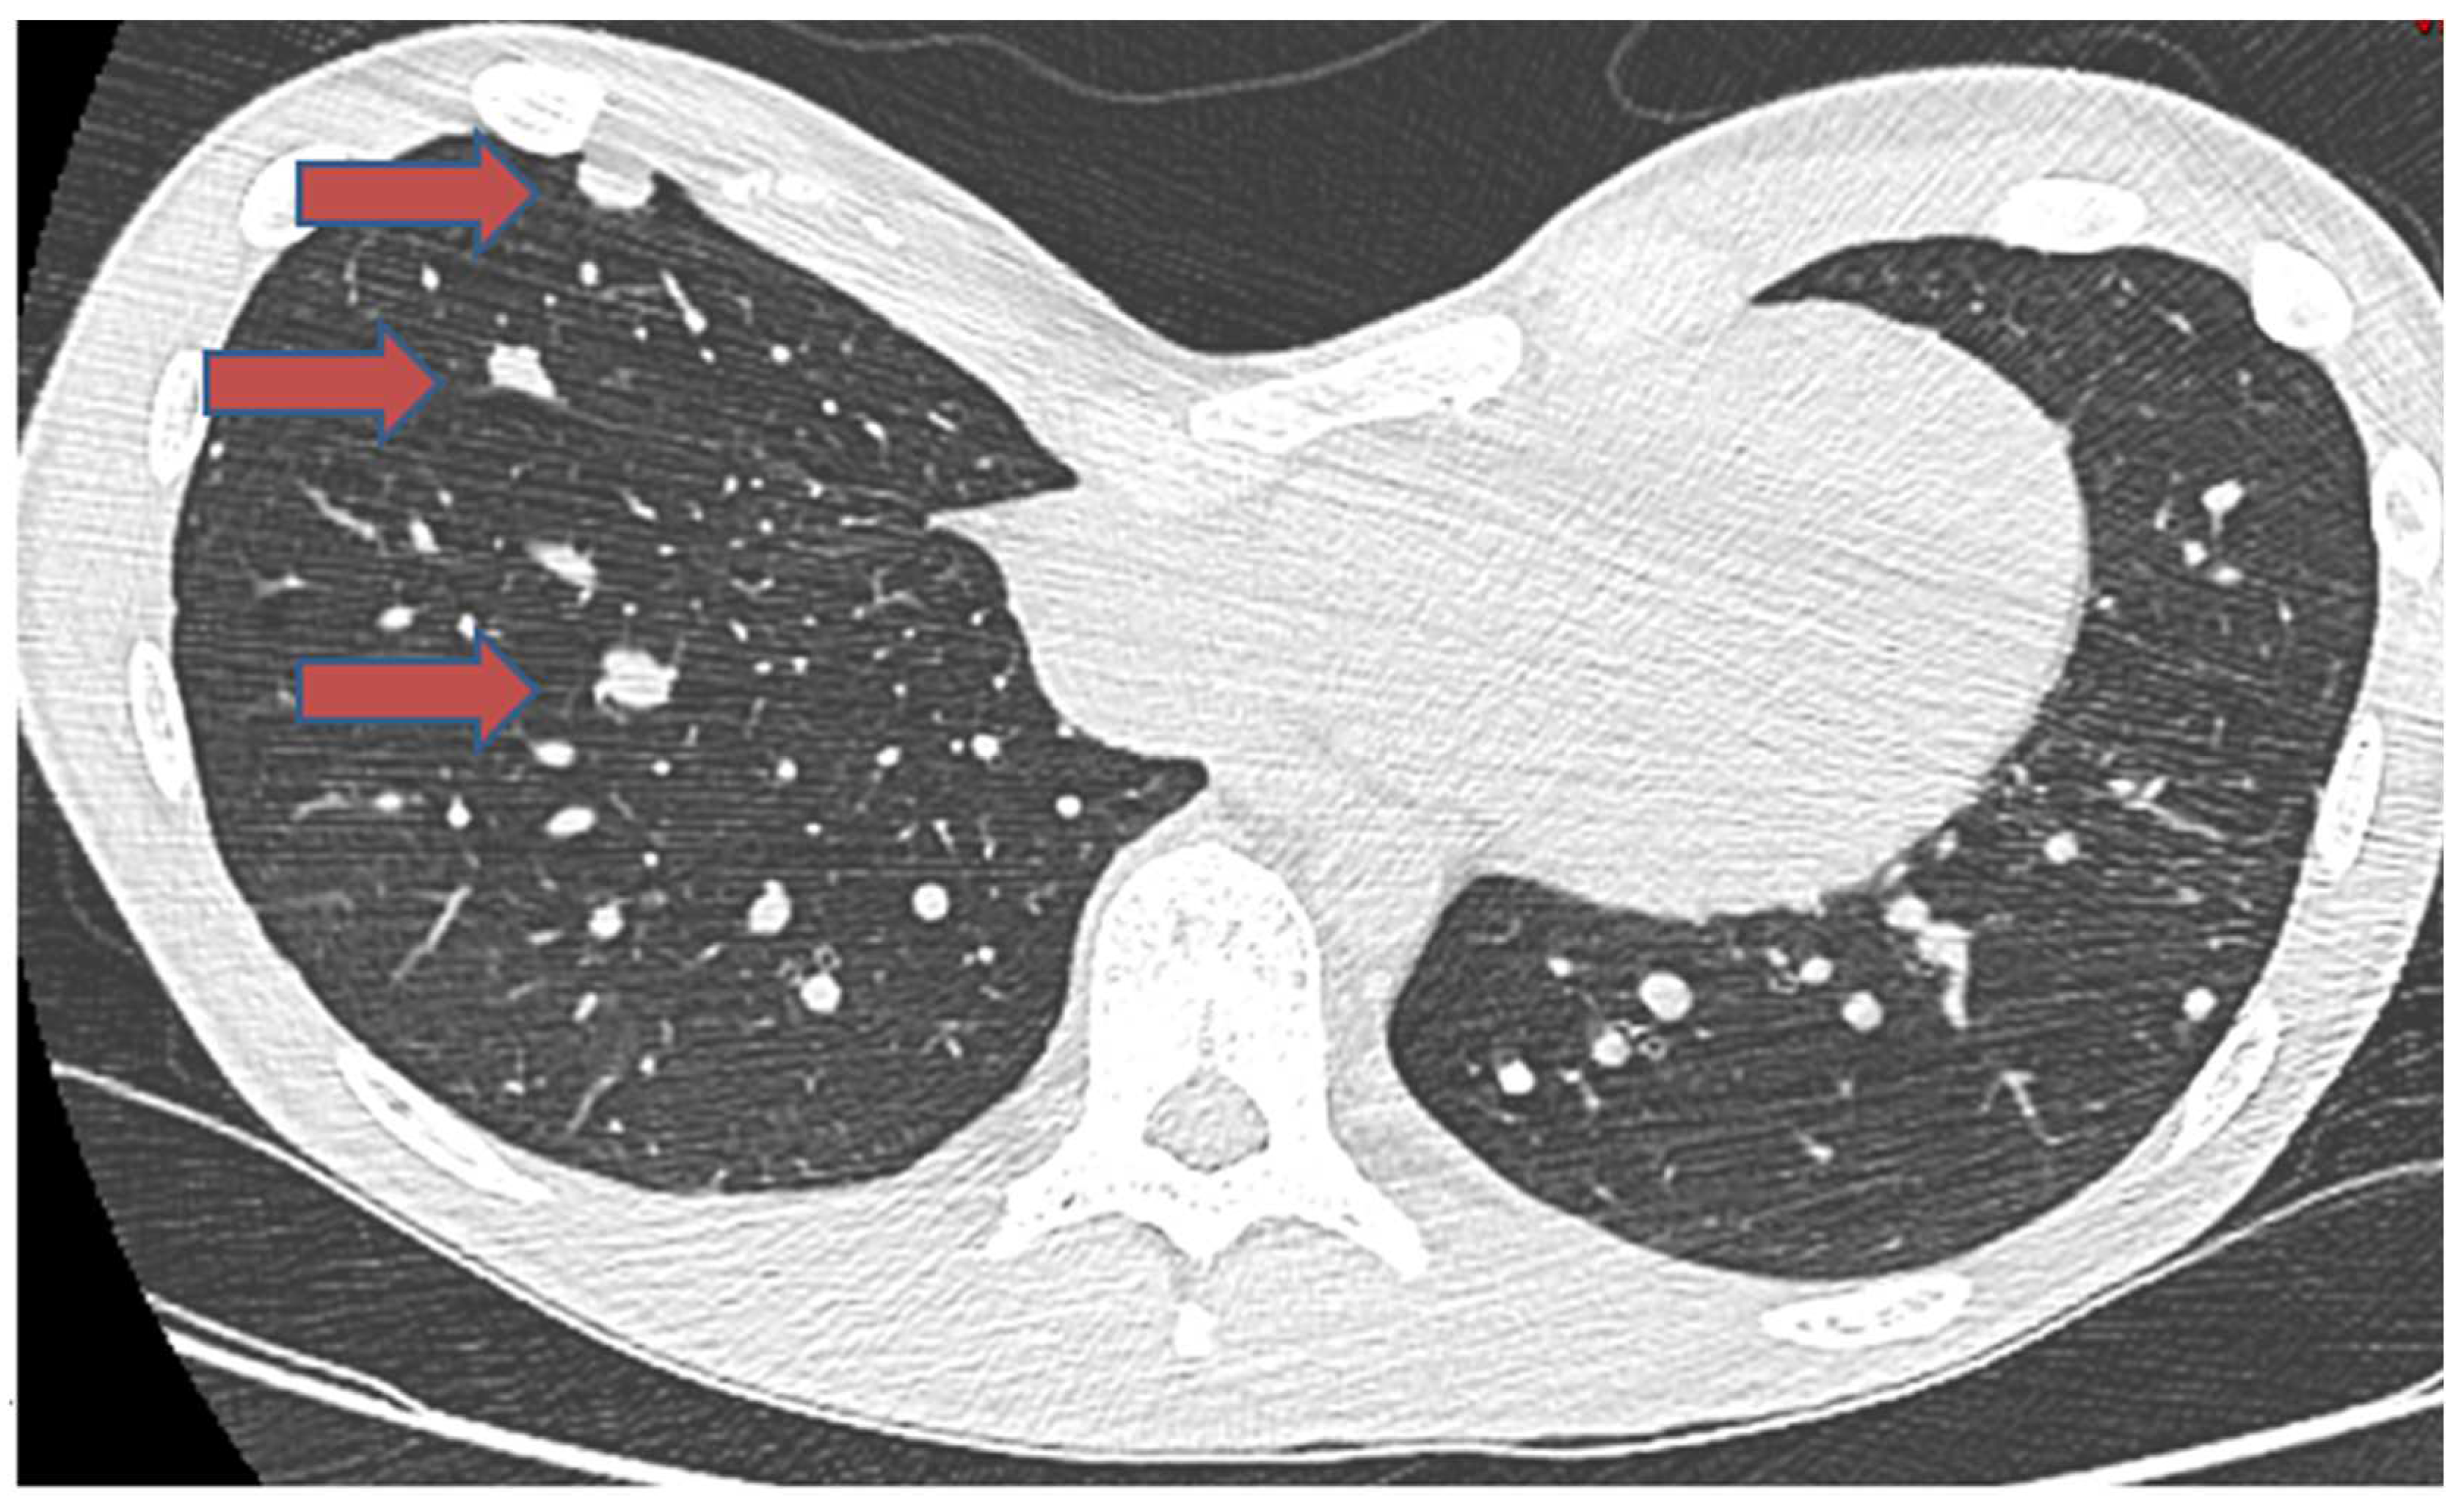

- Focaccia, M.; Gambarotti, M.; Hakim, R.; Paioli, A.; Cesari, M.; Spazzoli, B.; Spinnato, P.; Donati, D.; Rocca, M.; Longhi, A. Chondroblastoma’s Lung Metastases Treated with Denosumab in Pediatric Patient. Cancer Res. Treat. 2021, 53, 279–282. [Google Scholar] [CrossRef] [PubMed]

| Focaccia. M. [37] | 16/M | Proximal humerus | Lung | Occurred at initial diagnosis | Benign | 2 years | Alive at final follow-up | Denosumab treatment | |